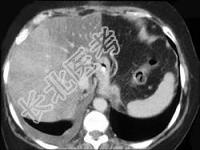

- 单项选择题男,66岁, 肥胖,有糖尿病史, CT检查如图,最可能的诊断是 ( )

A、局灶性脂肪肝

B、肝硬化肝癌

C、肝血管瘤

D、肝胆管细胞癌

E、肝淋巴管瘤